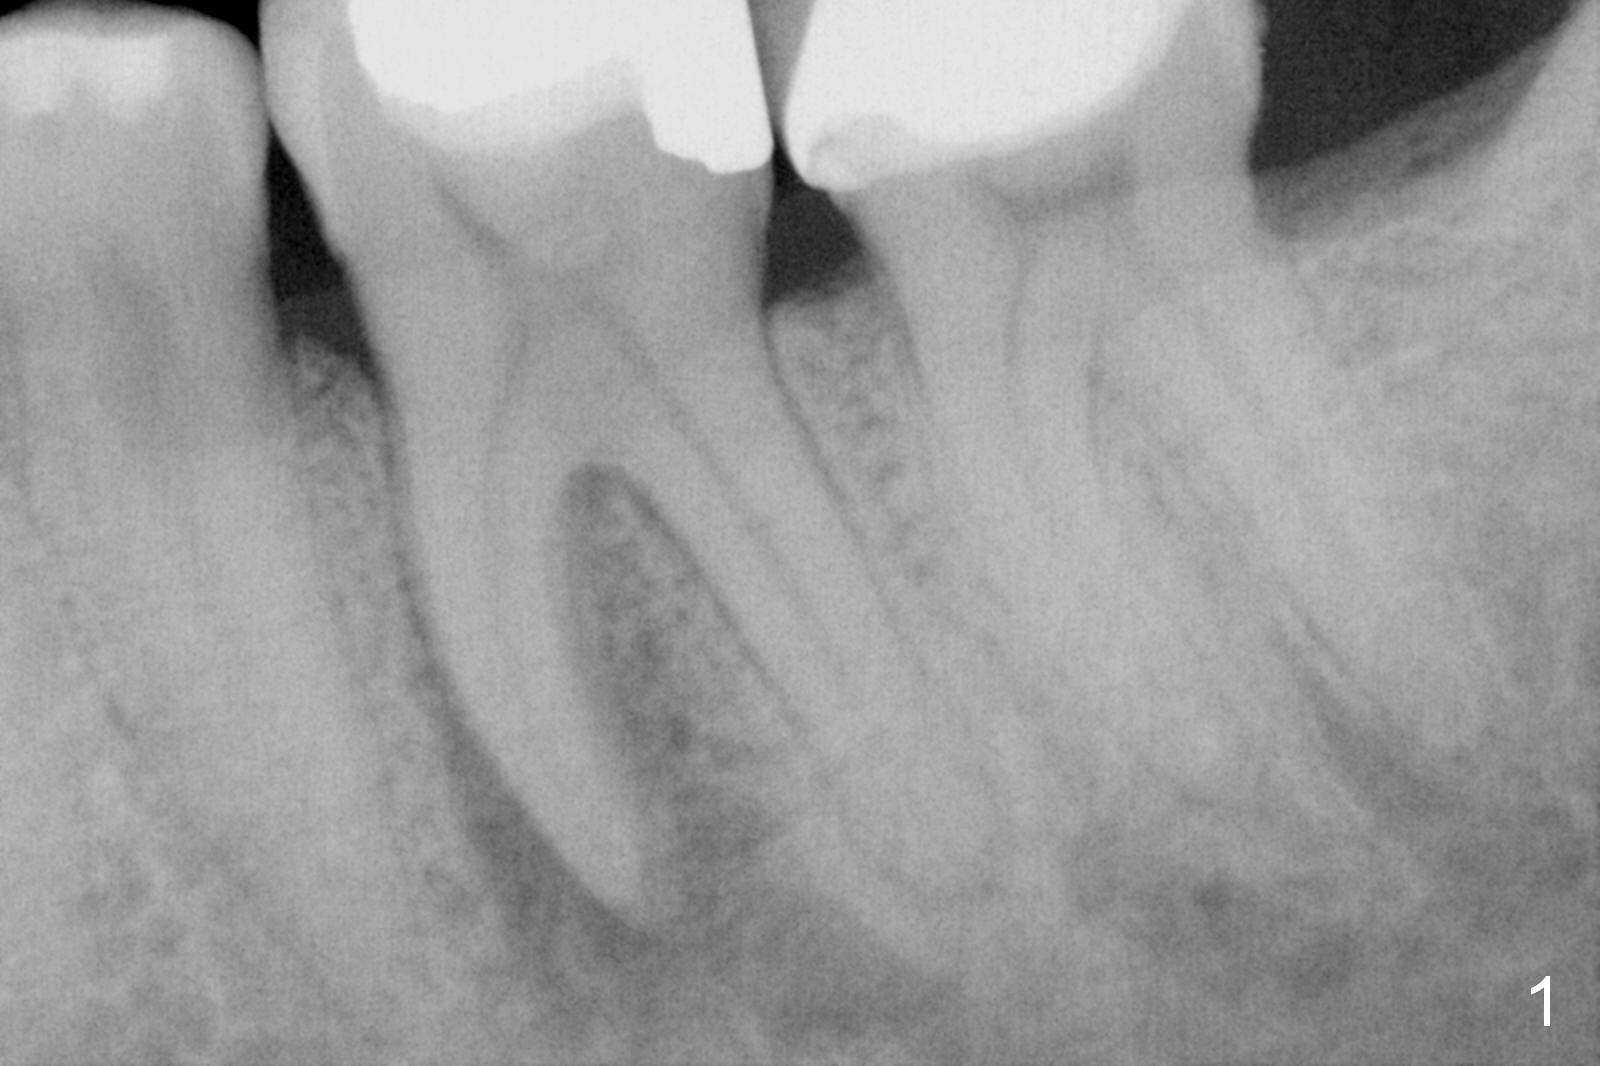

A 50-year-old man had pulpitis at #19 six years ago (Fig.1).  RCT looks well filled (Fig.2).  Recently he returns with severe toothache, involving the tooth #20 (Fig.3).  There is no sign of crack tooth.  Endo referral is recommended, but he would rather have it extracted first, since he is going to buy insurance near the end of the year for implant.  He returns for extraction, since he could not sleep well the previous night.  After block and periodontal ligament injection with two carpules of Lidocaine, extraction proves to be painful.  A carpule of Marcaine is administered for block.  While waiting for anesthesia to settle in, he suddenly agrees for immediate implant, since he had history of failure of bone graft after extraction at #30.  The site needs regraft.  The whole treatment takes two years.

The tooth #19 is easy to get loose, but it cannot be luxated.  After sectioning and extraction (Clindamycin), the septum is found to be thin (Fig.4).  A surgical fissure bur is used to initiate osteotomy, followed by 1.6 mm pilot drill.  It is difficult to use Marking bur (wobbling over the basically pointed septum).  It is impossible to use 4.3 mm Magic Drill (MD, one drill system), since it jumps.  The smallest MD has to be used (2.8 mm).  When the next drill (3.3 mm) is being used for 13 mm with stopper (Fig.5), the patient experiences transient pain.  The depth is suggested from the design in Fig.2.  The thin septum appears not to be a reliable landmark.  When block anesthesia is administered, the initial depth should be shortened.  The drill appears to be close to the Inferior Alveolar Canal (Fig.5).  Then the depth changes to 11 mm with the following drills (3.8 and 4.3).  The mesial and distal walls of the septum are gradually perforated.  A 5x9 mm dummy implant is placed only after using 4.8 mm drill (Fig.6).  The implant appears to be short.  When a longer implant is placed (5x11 mm), it does not easily enter the osteotomy, either sliding into the mesial or distal socket with the implant separating from the implant driver.  It appears that a premount implant is appropriate in this situation.  When the 5x11 mm implant is finally seated with stability, it is 6 mm apical to the gingival margin.  The longest cuff of IBS abutment is 4 mm.  A longer implant is needed (Fig.7, 5x13 mm).  Placement is not easy as mentioned above.  Insertion torque is <20 Ncm when the patient experience a little discomfort.  A 6.5x4(4) mm pair abutment is placed (A), apparently proper for restoration.  Allograft is placed (Fig.8 *) prior to immediate provisional.  The patient complains of bad smell from the site 24 days postop.  When the provisional is removed, the abutment is found to be mobile.  When the latter is removed with local anesthesia, bone graft granules are attached to the socket above the lightly mobile implant (Fig.9).  In fact the latter appears to be stable after a few turns by finger.  A healing screw is placed; the socket is closed with collagen plug and 4-0 Chromic gut sutures (Fig.10).  It appears that a larger implant should have been used to achieve higher torque.  Two months later (3 months postop), the coronal end of the implant is partially exposed.  A 5x4 mm healing abutment is placed.  It appears that the implant is stable.  The implant appears to have osteointegrated 4 months postop (Fig.11).  Impression is taken.